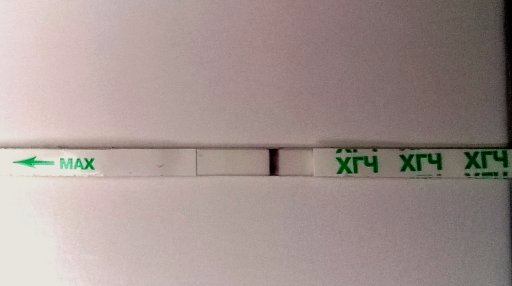

10-11дпо

Купила вчера тест мне неизвестный

Первый ответ Ева

вроде как он реагентит?

ну и видите что-нибудь?

не знаю, но реагенты просто так не бывают, сделай еще другой тест, на всех одновременно не могут быть реагенты

Вечерние не делала? Жуть как интересно)!!)))